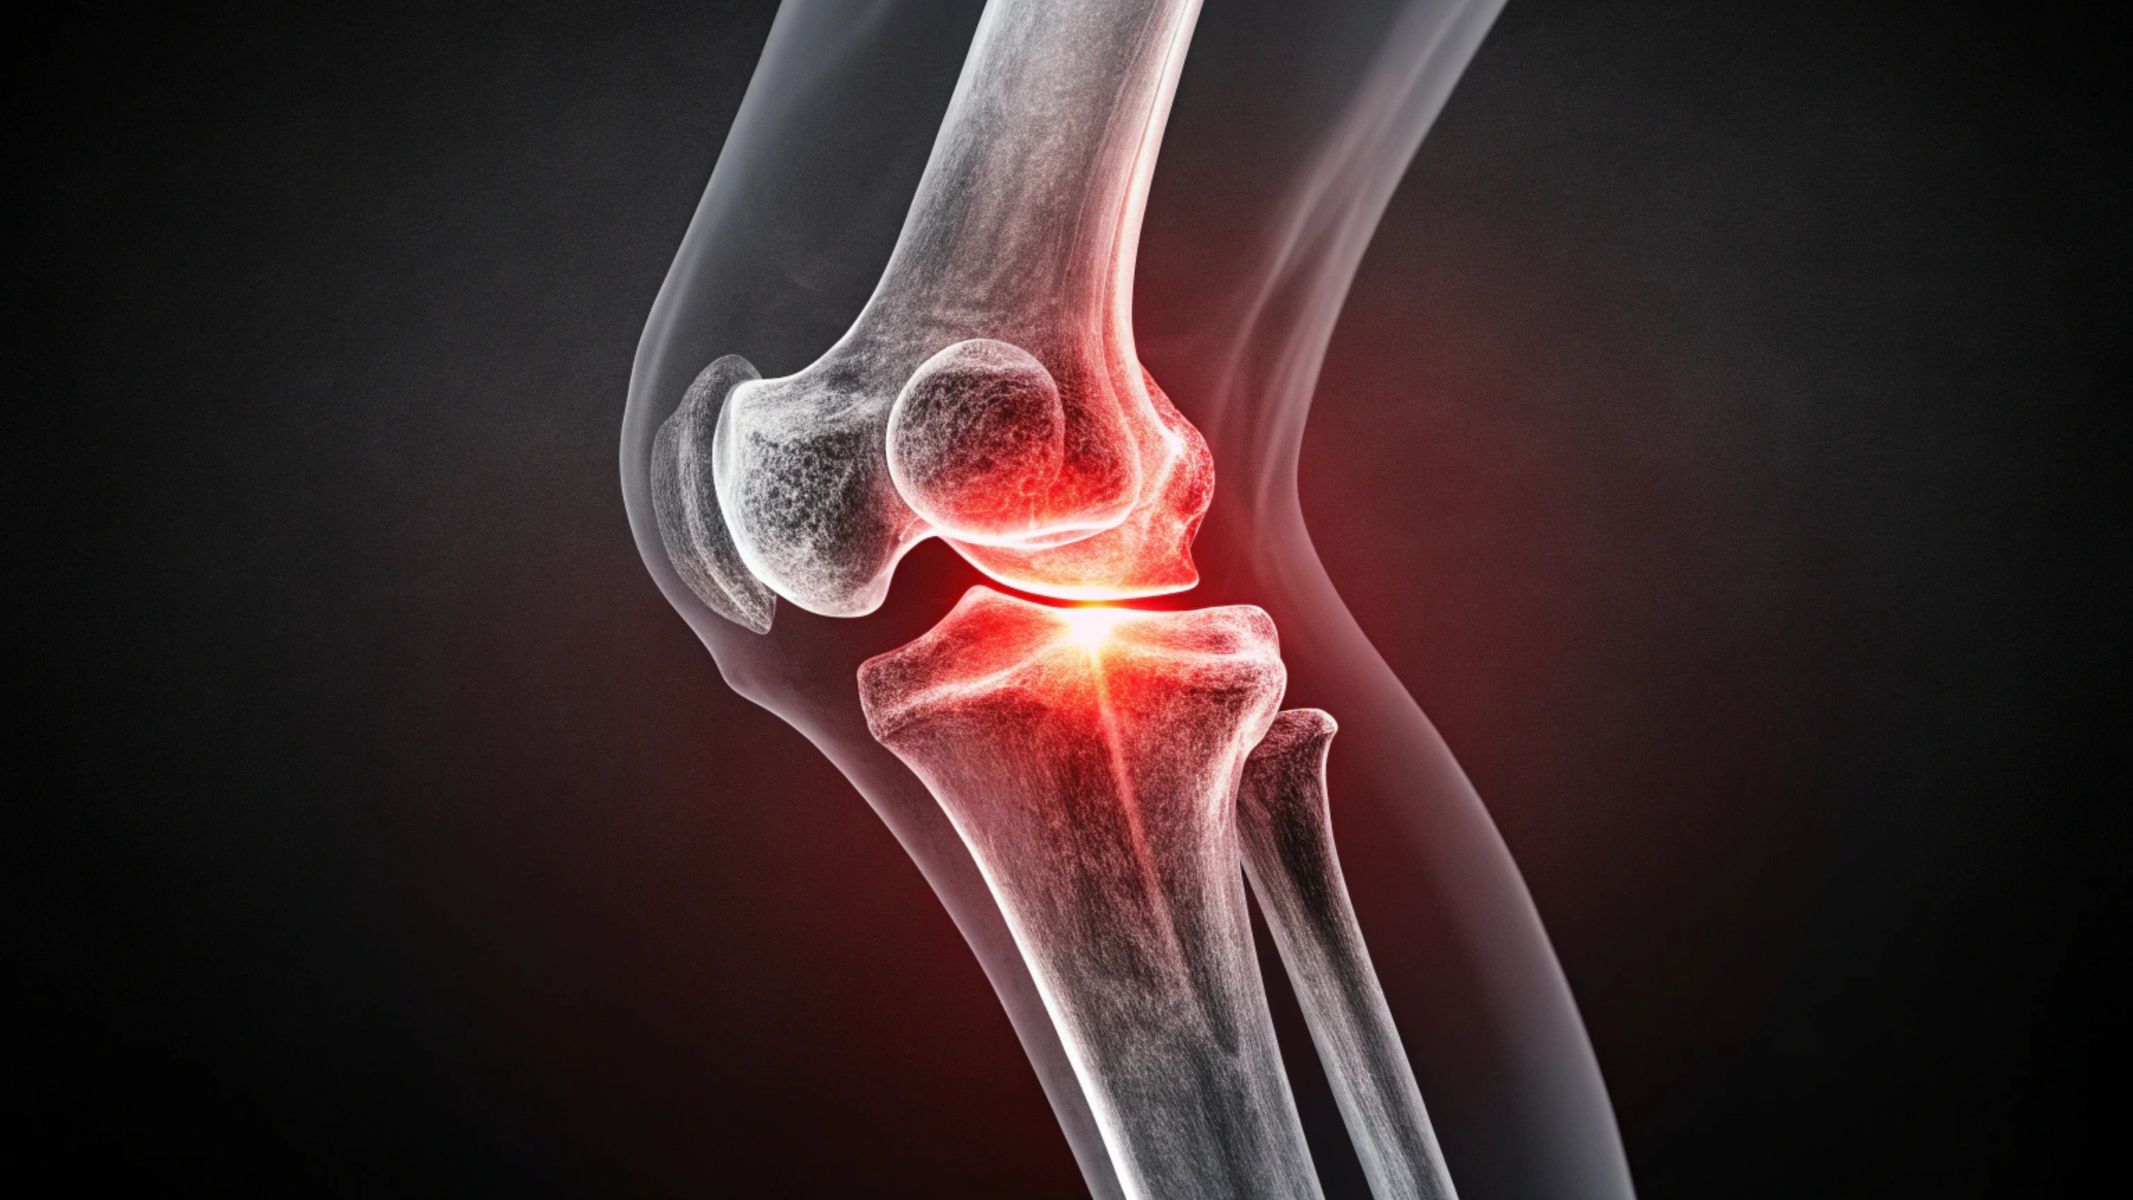

Chụp cộng hưởng từ (MRI) khớp gối là kỹ thuật chẩn đoán hình ảnh sử dụng từ trường mạnh kết hợp sóng radio để tạo ra hình ảnh chi tiết của toàn bộ cấu trúc khớp gối. Bao gồm xương, sụn khớp, sụn chêm, dây chằng, gân và các mô mềm xung quanh.

Khác với X quang chỉ đánh giá được cấu trúc xương, MRI cho phép quan sát rõ các tổn thương phần mềm. Đây là yếu tố đặc biệt quan trọng trong các bệnh lý khớp gối vì phần lớn tổn thương xảy ra ở dây chằng và sụn chêm.